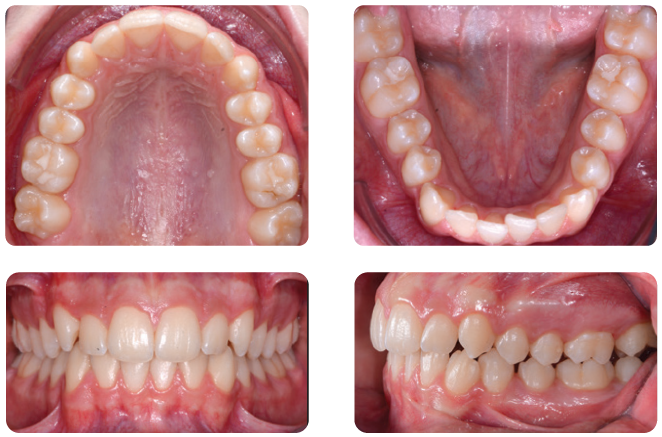

Clear aligner therapy has been shown to be effective in resolving mild to moderate malocclusions, with shorter treatment and less chairtime compared to conventional systems¹. To overcome some of the aligners’ biomechanical limitations while still enabling aesthetic treatment of more complex clinical conditions, clear aligners can be combined with various types of auxiliaries [2-4]. Let’s look at the case of an 14-year-old male patient with Class II relationship on right and edge-to-edge relationship on left before treatment.

Below picture before treatment.